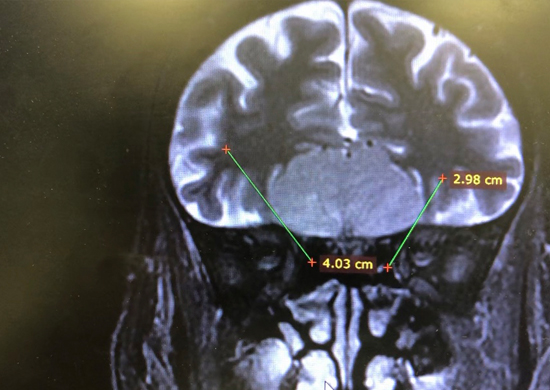

The Department of Surgery at the American University of Beirut Medical Center (AUBMC) performed the first Endoscopic Endonasal resection of large olfactory groove meningioma in Lebanon. The first- of-its-kind procedure permits the surgeon to remove tumors in the brain with less traction on it and better tumor control, providing a more advanced technique that allows patients a better quality of life.

The surgery was performed by Dr. Houssein Darwish, Brain and Spine Surgeon, Division of Neurosurgery, Department of Surgery at AUBMC assisted by Ear, Nose, and Throat (ENT) surgeon, Dr. Zeina Korban. These kinds of tumors, skull base tumors, were previously performed through a major craniotomy (open brain surgery). By applying this novel approach for the first time in Lebanon, the team resected the large olfactory groove meningioma without resorting to opening the patient’s skull and brain; instead, they used an endoscope and accessed the tumor only through the nose.